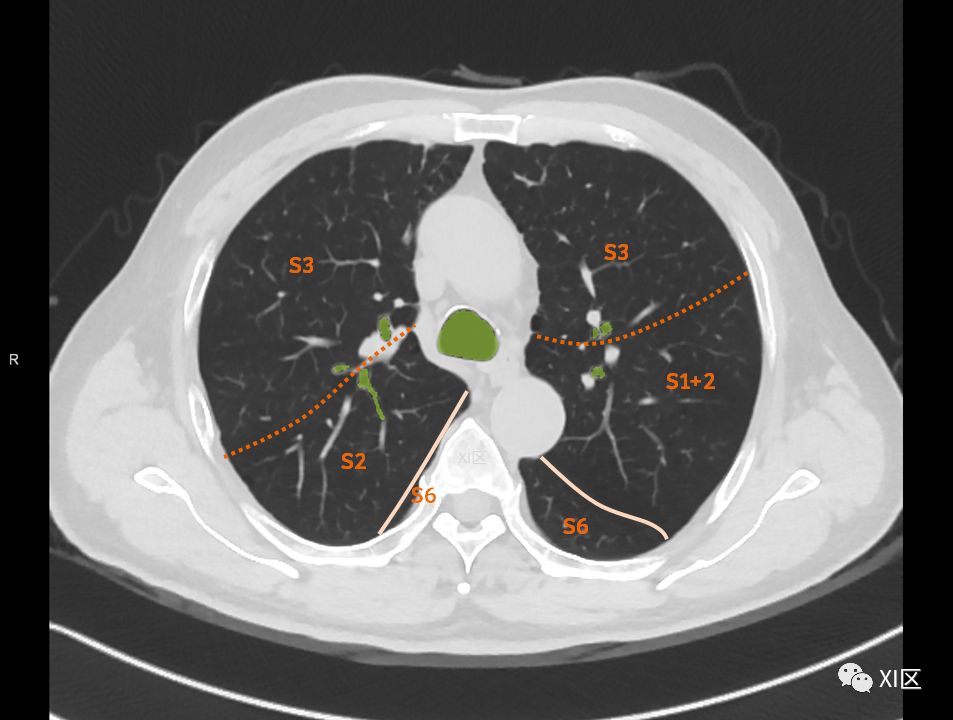

在进行肺的分段时,可以上下观察浏览,沿着相应气管的走形可以更容易准确地进行分段。

肺的分段

肺的断层分段示意图